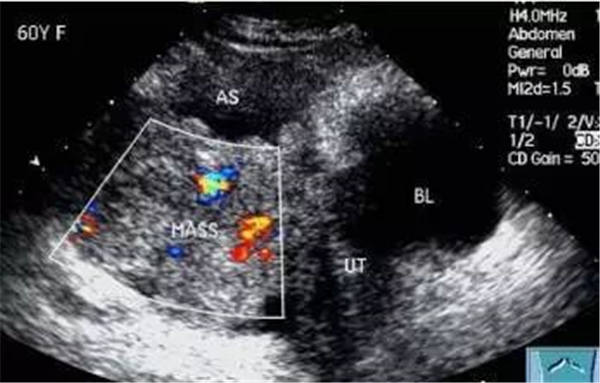

血栓

血栓是血栓性肺栓塞最典型的特征,位于右房或右室中的血栓可形态各异,而位于肺动脉内时则常表现为大块血栓,从主干延续至一侧或双侧肺动脉分支。右肺动脉主干血栓易于显示,左肺动脉因显示较短,血栓不易显示。此外,需注意将血栓与右心系统肿瘤相鉴别。

右心血栓 肺动脉血栓